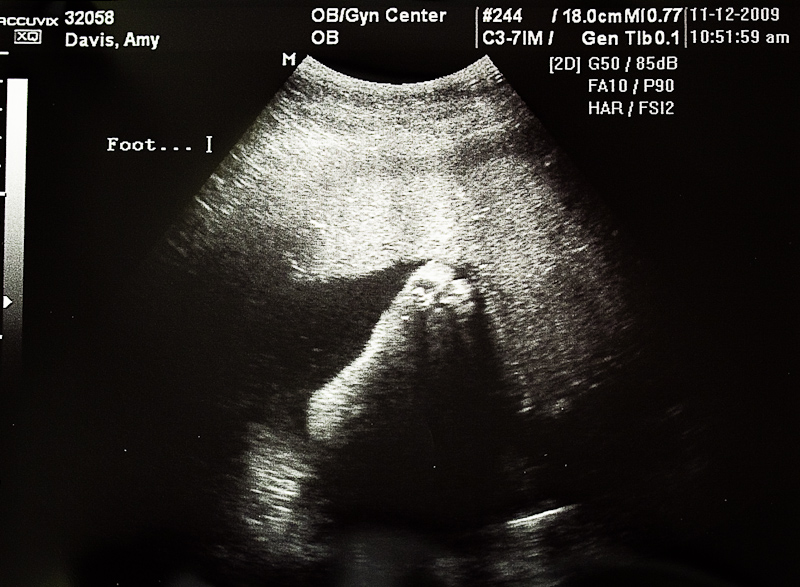

35 Week Ultrasound Feet

Baby Boy's Feet at 35 Weeks